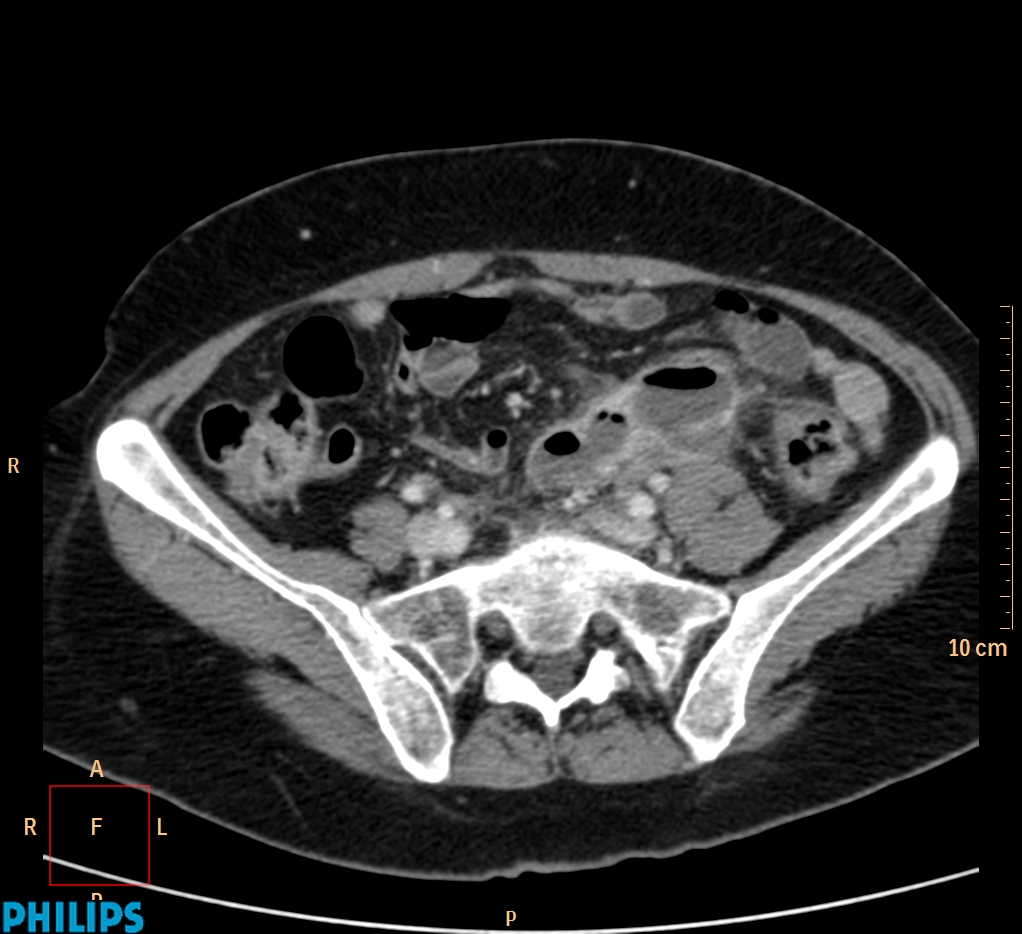

ΕΚΚΟΛΠΩΜΑΤΑ ΠΑΧΕΟΣ ΕΝΤΕΡΟΥ Posted by ΙΠΠΟΚΡΑΤΕΙΟ ΙΩΑΝΝΙΝΩΝ | Dec 16, 2020 | ΠΕΠΤΙΚΟ | 0 ΚΛΙΝΙΚΑ ΣΤΟΙΧΕΙΑ – ΙΣΤΟΡΙΚΟ υποτροπιάζοντες επαναλαμβανόμενοι πυρετοί κυρίως απογευματινές ώρες ΕΡΓΑΣΤΗΡΙΑΚΟΣ ΕΛΕΓΧΟΣ ΑΠΕΙΚΟΝΙΣΤΙΚΟΣ ΕΛΕΓΧΟΣ διακρίνονται τα αποστήματα στην ελάσσονα πύελο, καθώς και εκκολπώματα με εικόνα πάχυνσης του τοιχώματος του σιγμοειδούς ΣΥΖΗΤΗΣΗ